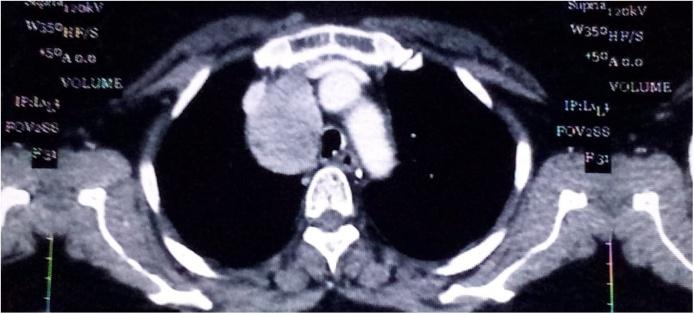

This is a 59-year-old women, followed for glaucoma and operated for bilateral congenital cataract reffered to our structure by the service of pnemology for a right laterotracheal mediastinal mass. The patient presented respiratory symptoms over four months, and the physical examination found patient in good condition with PS 0 and normal vital signs, a poor oral health was noticed. The CT scann showed a left basal opacity and a right laterotracheal mediastinal mass at the upper right mediastinum, pushing forward the superior vena cava and compressing the trachea on the contralateral side, with well-defined borders and without signs of infiltration of adjacent structure. The brochoscopy was perfomed which showed the yellowish granulous aspect and the pathophysiology revealed a pulmonary actinomycosis. The patient was treated with antibiotic based on parenteral infusion of penicillin G at 20 million / day for 6 weeks relayed by oral administration of 3 g / day for 3 months with a good response and the left basal opacity disappeared on the CT control but the mediastinal mass persisted. After multidisciplinary concertation, the mediastinoscopy was perfomed and has revealed an ectopic thyroid which was removed by Uniportal Videoassisted Thoracoscopic Surgery (U-VATS) approach.

这是一名59岁女性,因青光眼接受随访,因双侧先天性白内障接受手术,由呼吸科转诊至我院,以评估右气管旁纵隔肿块。患者出现呼吸道症状四个多月,体格检查发现患者状况良好,体力状况评分为0,生命体征正常,但口腔卫生较差。CT扫描显示左肺底部有模糊影,右上纵隔有右气管旁纵隔肿块,向前推移上腔静脉并压迫对侧气管,边界清晰,无相邻结构浸润迹象。进行了支气管镜检查,显示为淡黄色颗粒状外观,病理生理学显示为肺放线菌病。患者接受了抗生素治疗,静脉输注青霉素G 2000万单位/天,持续6周,随后口服3克/天,持续3个月,反应良好,CT复查显示左肺底部模糊影消失,但纵隔肿块仍然存在。经过多学科会诊,进行了纵隔镜检查,发现是异位甲状腺,通过单孔电视辅助胸腔镜手术(U-VATS)方法将其切除。